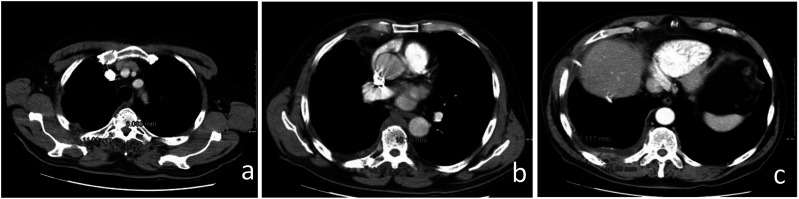

Background: Malignant pleural mesothelioma is the most common primary tumor of the pleura. The unique growth pattern of malignant pleural mesothelioma makes it difficult to apply the Response Evaluation Criteria for Solid Tumors (RECIST). Hence the need to use modified RECIST (mRECIST) criteria, as they better fit the unique growth pattern of malignant pleural mesothelioma. The thickness of the tumor perpendicular to the chest wall or mediastinum is measured at 2 points at 3 separate levels at least 1 cm apart on chest CT scans, and summed to obtain a one-dimensional pleural measurement. The same criterion has also been used to assess response to treatment. RECIST 1.1 represents a further update, taking into account new concepts such as revised minimum dimensions for lymph nodes and an approach to lesions that become non-measurable. Based on experience and published literature, the hypothesis of merging the 2 above-mentioned criteria in mRECIST 1.1 for mesothelioma and the use of iRECIST for the application to immune-based therapies (iRECIST) was considered. Purpose: Support the importance of studying pleural mesothelioma in a reliable and reproducible way, through a scrupulous methodology, applying the mRECIST1.1 and iRECIST criteria. Conclusions: Adoption of a standardized study metodology can make the study of PM reproducible and correct.

Abstract Image